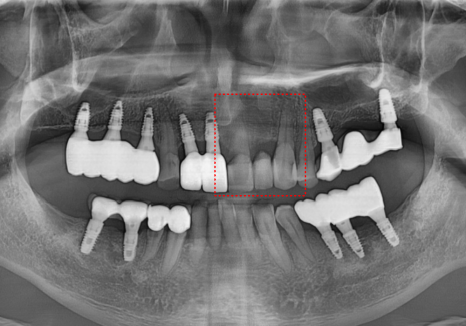

먼저 충치가 심했던 앞니(#21)부터

치료를 시작했습니다.

충치를 깨끗하게 걷어내고,

감염된 신경을 제거하는

신경치료를 꼼꼼하게 진행했죠.

#21 신경치료 과정

워낙 충치가 깊어서 걱정했지만,

다행히 신경치료가 잘 마무리되어

치아를 살려 쓸 수 있게 되었습니다.

그리고 바로 이어서 수술을 진행했는데요.

브릿지 연결 부위였던 치아 없는 자리는

다행히 잇몸 뼈가 아주 튼튼했습니다.

230614

덕분에 환자분이 힘들어하시는

뼈이식 과정 없이,

아주 수월하게 임플란트를 식립할 수 있었죠.

하지만 임플란트가 뼈와 붙기까진

시간이 필요하기에,

그동안 일상생활에 지장이 없도록

임시 치아를 예쁘게 만들어 드렸답니다. ^^